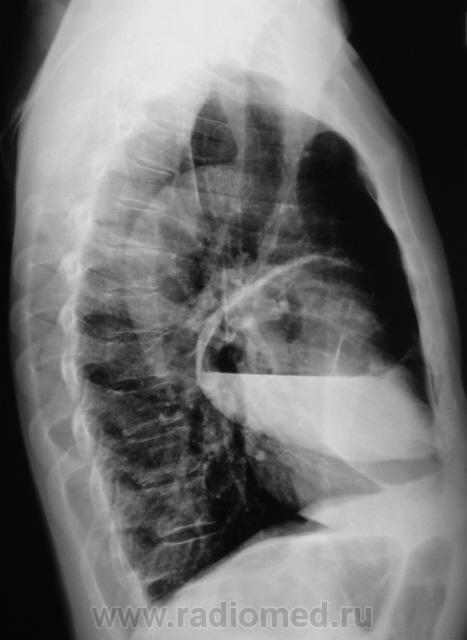

Произвели рентгенографию в стандартных проекциях.

Флюорограмма 2009 года.

сильно похоже на нагноившуюся кисту...

Она и есть.

Но, пациент жалоб не предъявляет...

Киста, точно киста. Был пациент на консультации у торакальщиков, будут готовить к плановой операции.

Клиника при блокированом абсцессе, а таковой и будет нагноившаяся киста - может быть весьма скудной; при "конкретном" допросе что то и выясниться...а если еще и промониторить пару дней, то нароется куча всего, что вполне и подойдет под такую штуку....Знаем мы их жалобы...типа - "у меня легкие"...."у меня желудок"...сто потов сойдет, пока рациональное ключевое слово не услышишь.